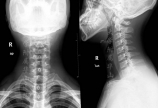

【脊柱其他】16岁平山病少年:双手肌肉萎缩

病情概述: 病例116岁,男,2017年2月7日入院。主诉:左手肌萎缩1年余,右手肌萎缩6月。查体:左手骨间肌肌萎缩,大鱼际萎缩明显,拇指无法背伸,手内肌力0-II级;右手肌肉萎缩,小手指伸直不能,手内肌力0-III级;双手握力减退,伸屈腕肌力减弱,IV级;双上肢近端肌力V… [详情]